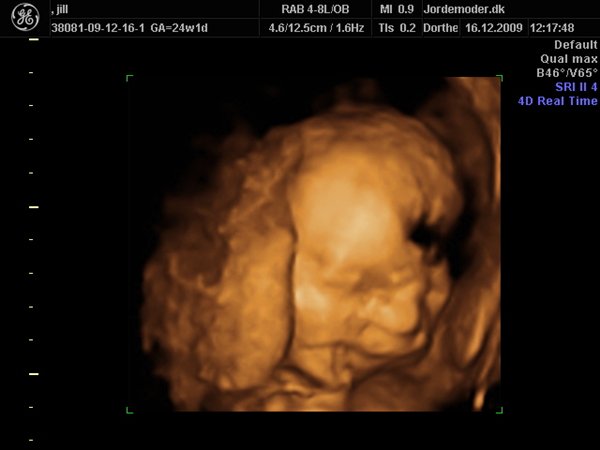

her er lidt fra vores scanning i uge 24+1, hun blev vurderet til 675 g....jeg synes det er vildt så mange detaljer og ansigsudtryk hun havde;-)

derfor glæder jeg mig til at se hende "rigtigt"....synes hun ligner mig som baby...hehe

knus jill